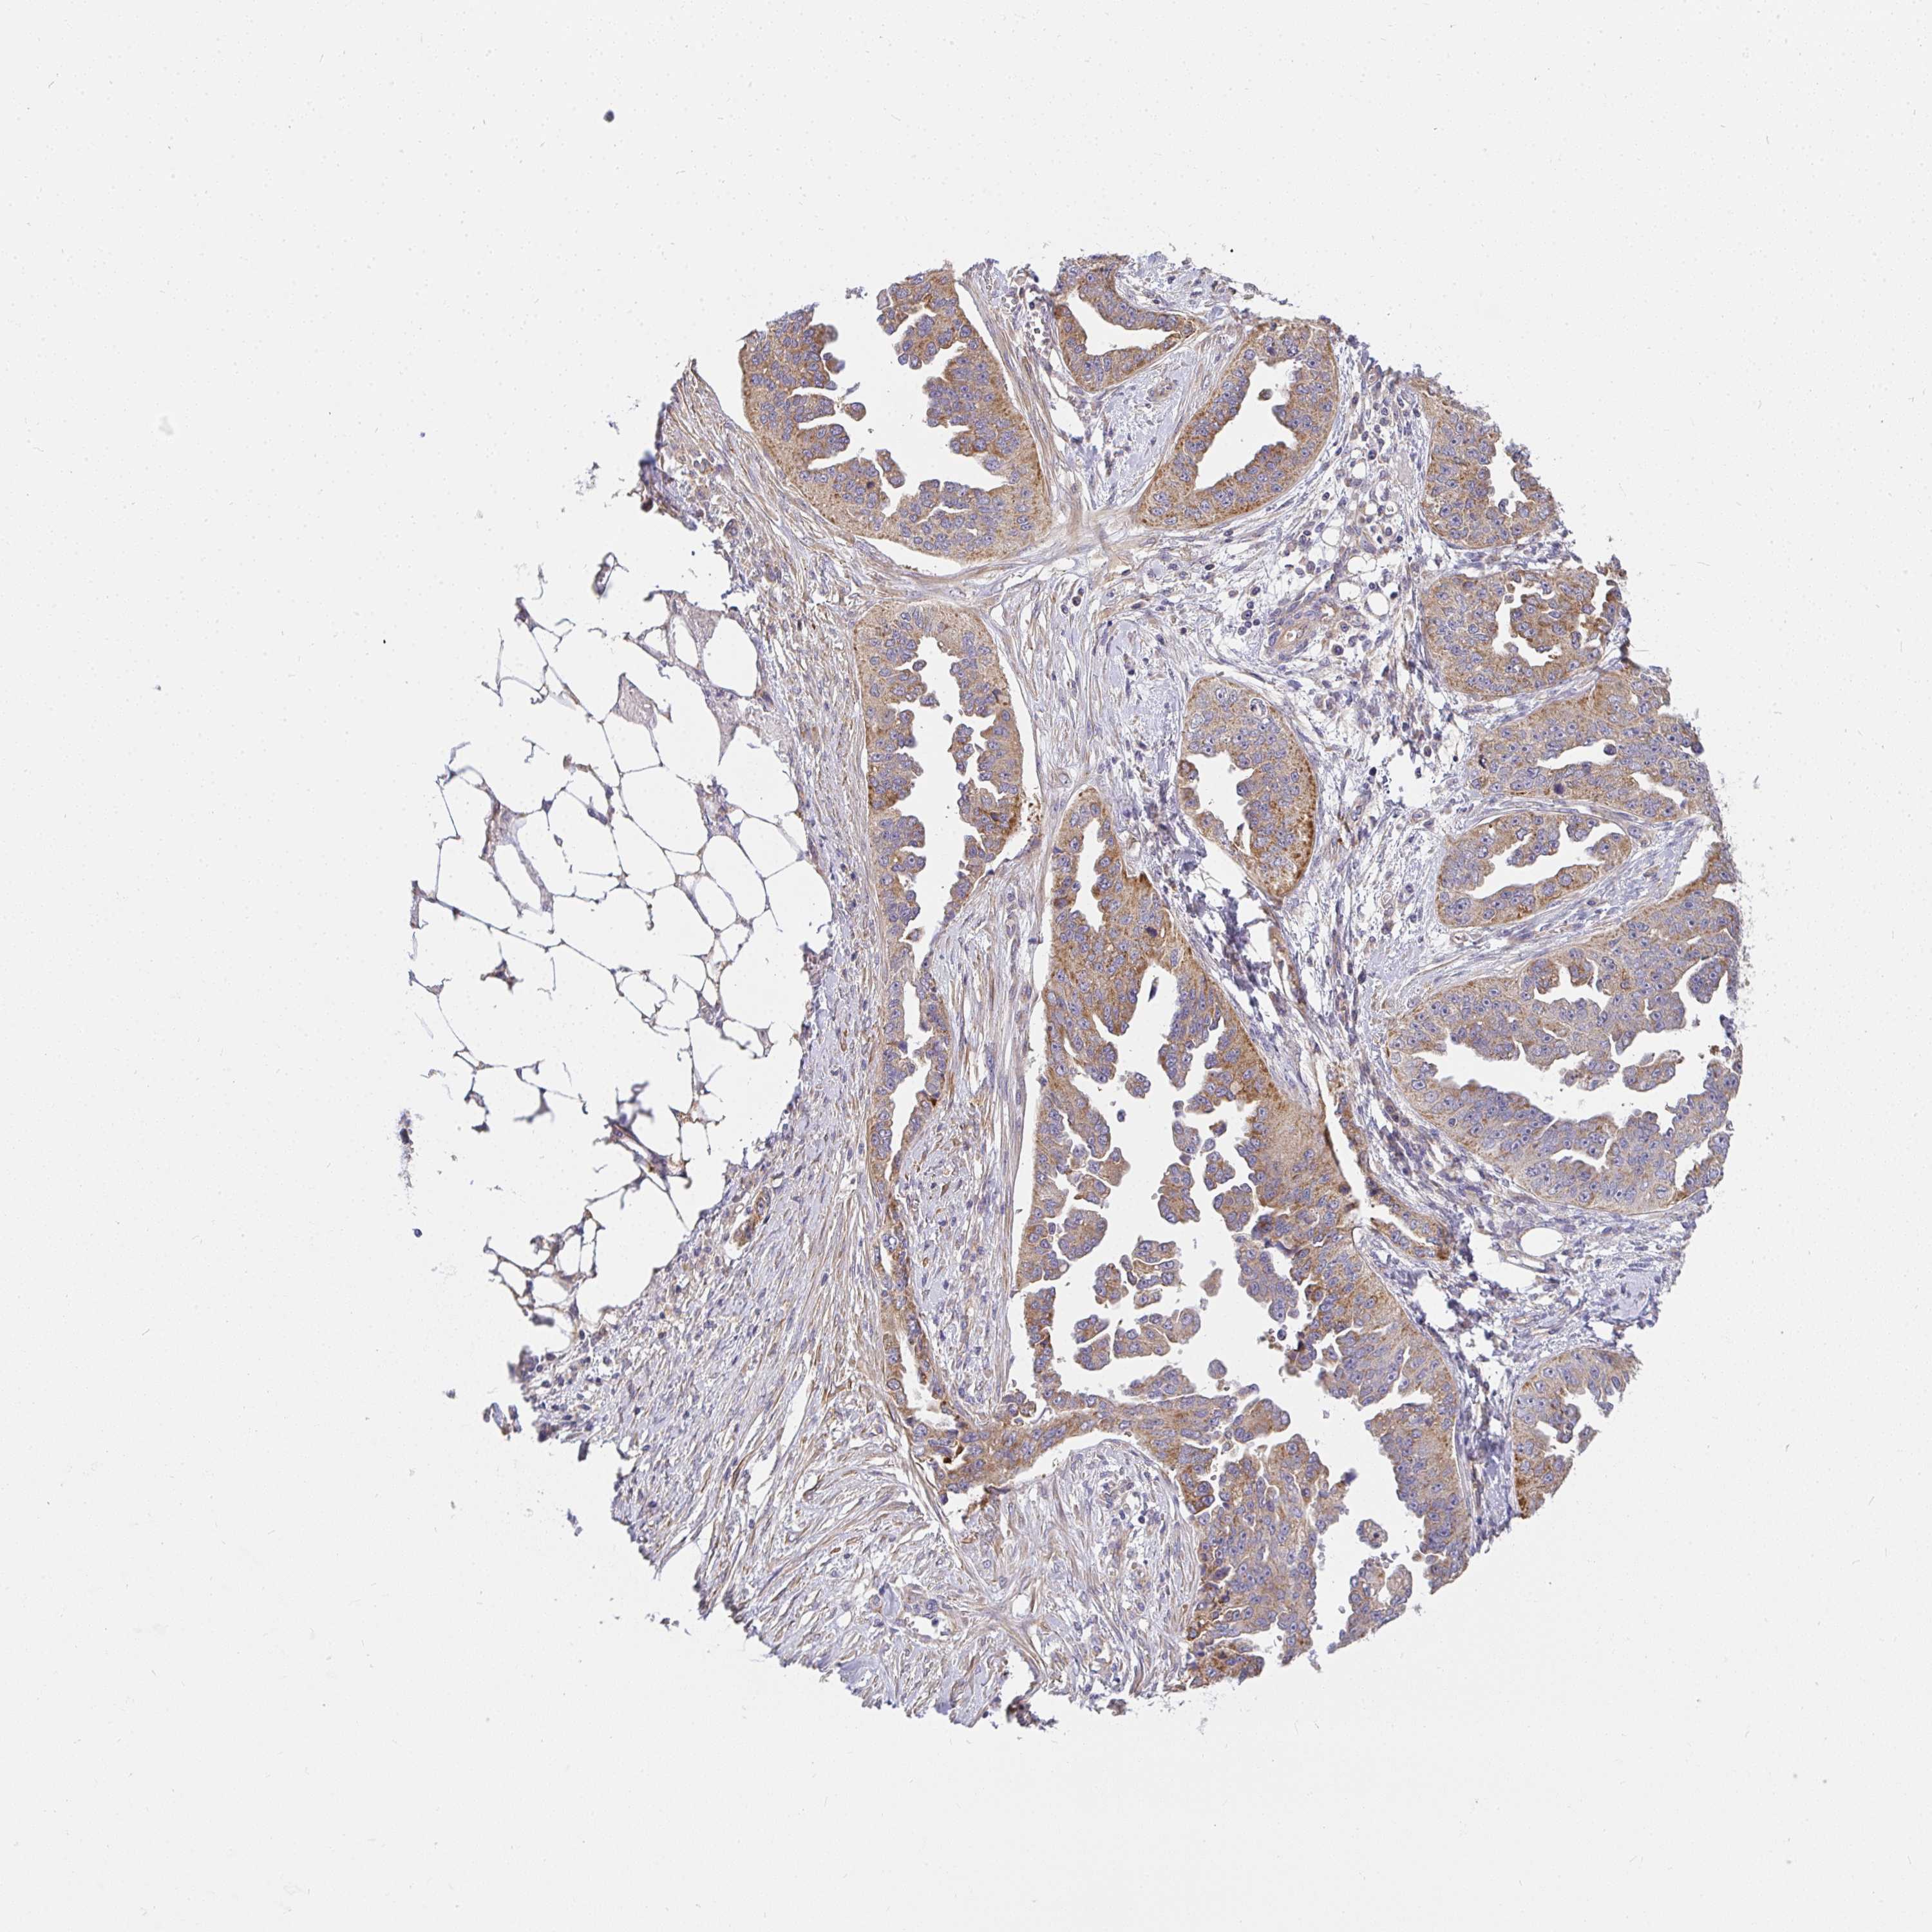

OVARIAN CANCER - Protein expressioni

A mouse-over function shows sample information and annotation data. Click on an image to view it in a full screen mode. Samples can be filtered based on level of antibody staining by selecting one or several of the following categories: high, medium, low and not detected. The assay and annotation is described here.

Note that samples used for immunohistochemistry by the Human Protein Atlas do not correspond to samples in the TCGA dataset.

Antibody stainingi

Antibody staining in the annotated cell types in the current human tissue is reported as not detected, low, medium, or high, based on conventional immunohistochemistry profiling in selected tissues. This score is based on the combination of the staining intensity and fraction of stained cells.

Each image is clickable and will lead to virtual microscopy that enables deeper exploration of all samples and also displays staining intensity scores, fraction scores and subcellular localization as well as patient and tissue information for each sample.

Antibody HPA058284

Antibody CAB020701

Staining

High

Medium

Low

Not detected

Intensity

Strong

Moderate

Weak

Negative

Quantity

>75%

75%-25%

<25%

None

Location

Nuclear

Cytoplasmic/membranous

Cytoplasmic/membranous,nuclear

Cystadenocarcinoma, serous, NOS

Cystadenocarcinoma, mucinous, NOS

Carcinoma, endometroid